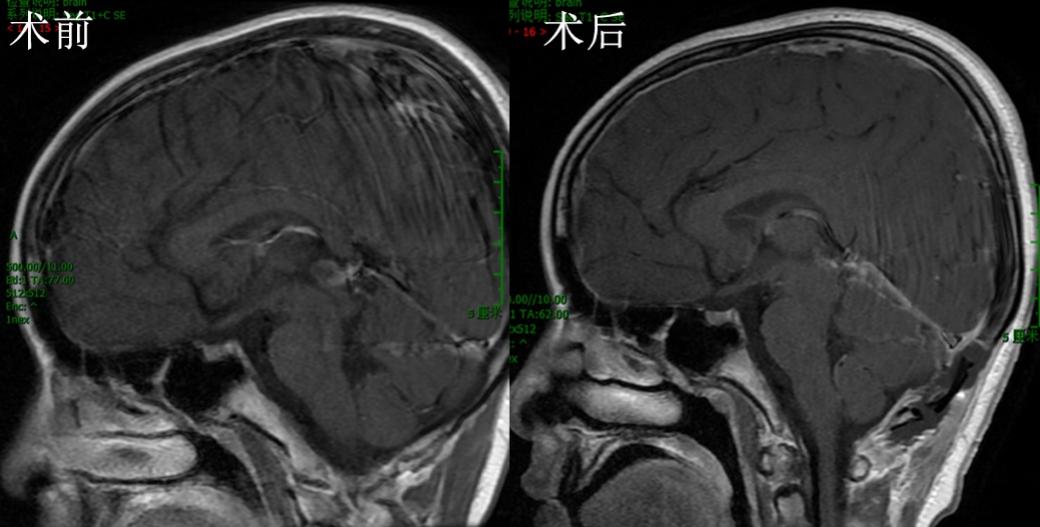

患儿方x,10岁9月,因“头痛、呕吐1月,外院行三脑室底造瘘术后2周”入院。患儿1月前无明显诱因下出现头痛,严重时伴有喷射性呕吐,就诊当地医院,检查发现松果体区占位、脑积水,行三脑室底造瘘术(图1)。术后患者头痛呕吐症状明显缓解,但新出现间断癫痫大发作,予以丙戊酸钠+氯硝西泮抗癫痫抗癫痫治疗,控制满意。就诊我院,神经系统查体未见明显异常。脑MRI检查提示松果体区占位(图 2A-C)。

图1,术前脑室稍扩大